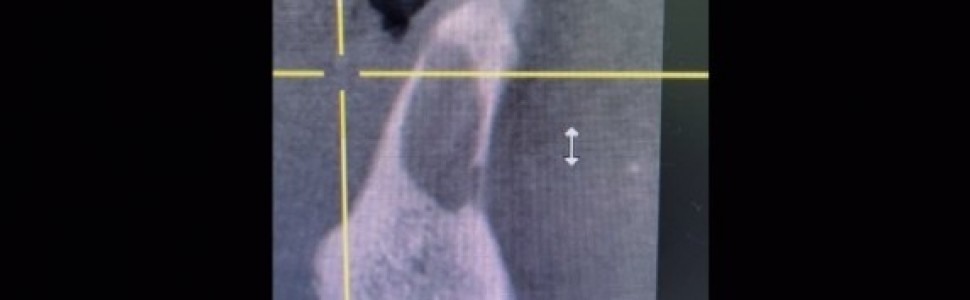

Film 3. CBCT płaszczyzna strzałkowa, zęby 31 i 41 (kwiecień 2021 r.).